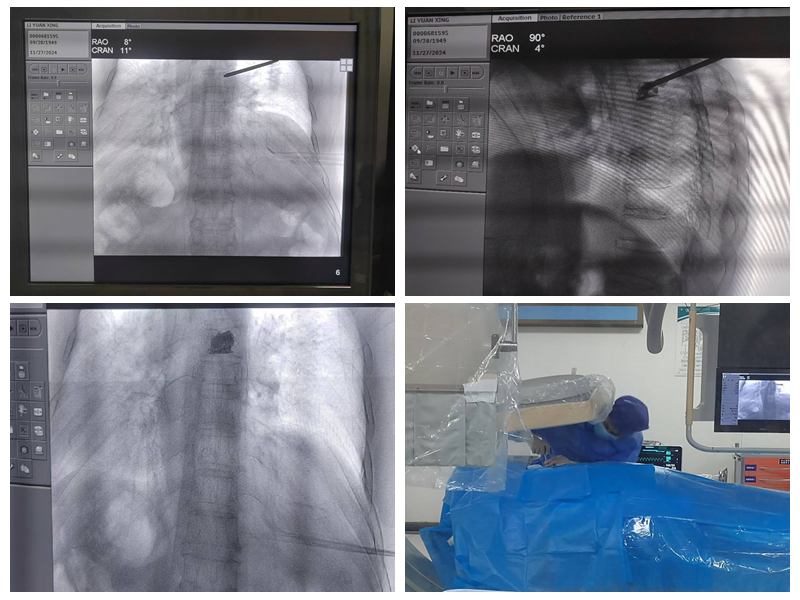

能完成该标准要求的绝大多数手术,包括选择性神经根阻滞技术、交感神经丛(干)介入医治技术、颅神经介入医治技术、神经射频调制技术、腰椎间盘介入医治技术、颈椎间盘介入医治技术、外周神经射频技术、脊髓电刺激、椎体成形术、硬膜外造影术、椎间盘造影术等。

脊髓电刺激